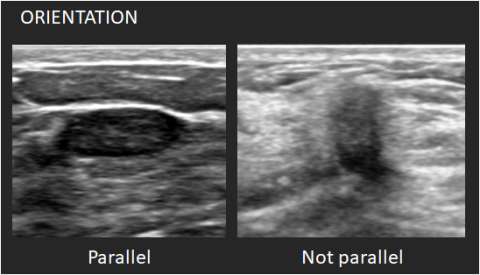

Orientation: Orientation is defined with reference to the skin line. Parallel or “wider-than-tall” orientation is often a characteristic of benign masses; however, it should not be the sole feature when assessing for likelihood of malignancy.

- Parallel: The long axis of the mass parallels the skin line.

- Not parallel: The long axis of the mass is not parallel to the skin line.